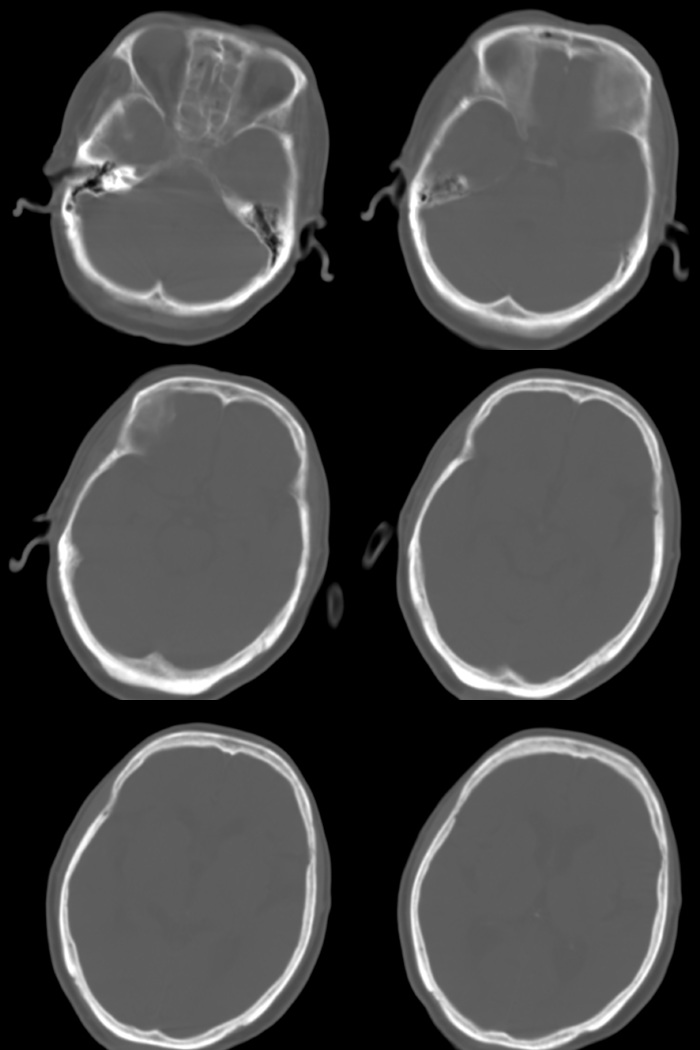

标题: CT17990:F76y,反复头昏。

76岁女性,反复头昏、头痛,余无不适。

诊断:右颞部钙化性脑膜瘤.

诊断依据:1.定位:脑外颅内--邻近脑沟增宽/脑组织受压内移/局部颅骨增生.

2.定性:良性--病灶边缘光整清楚/密度较高均匀/脑组织水肿不明显即占位效应不明显.

鉴别诊断:1.右颞骨内生骨软骨瘤/2.少突胶质细胞瘤/3.弥漫性星型细胞瘤.

1)考虑右颞部钙化性脑膜瘤。2)脑萎缩。

考虑脑膜瘤可能性大,如果是骨软骨瘤应该是广基底与颞骨相连,本例没有发现;当然应该在病灶范围内行薄层扫描进一步查明其与颞骨的关系对诊断有帮助。